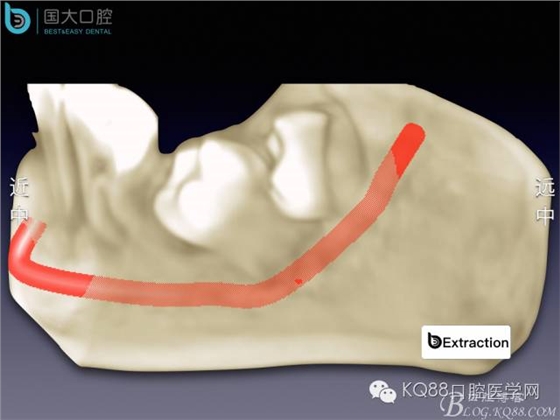

阻生牙的預(yù)防性拔除